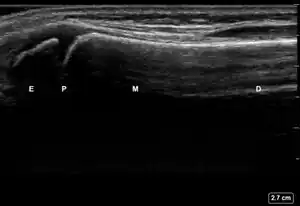

| 2 | Buckle (Torus) Fracture | "Bent" | ![]() Ultrasound dorsal view of buckle fracture of radius (shown by arrow). E = epiphysis; P = physis; M = metaphysis; D = diaphysis. | ||

| 3 | Cortical Break Fracture | "Broken" | Break, step or gap in bone cortex which appears as a black zone in the bright, sharp white line[10][11][14][15][16] | ![]() Ultrasound dorsal view of cortical break fracture of radius (shown by arrow). E = epiphysis; P = physis; M = metaphysis; D = diaphysis. |